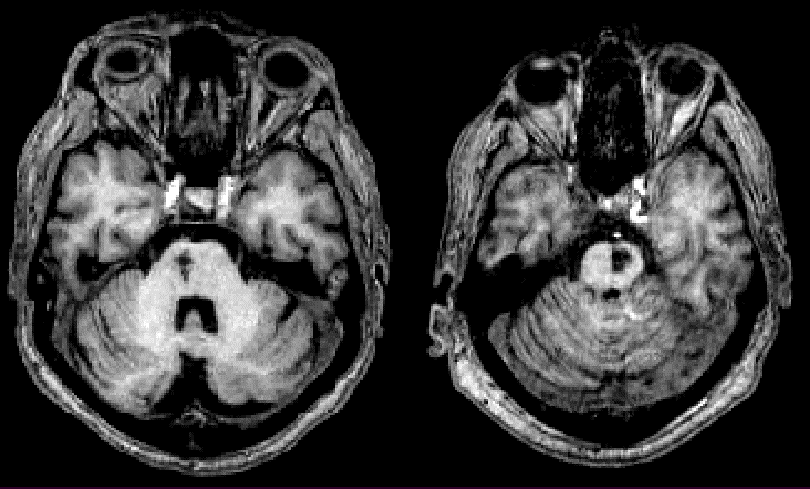

Tuần hoàn trước:

Từ động mạch cảnh trong

- Động mạch não giữa (MCA): liệt nửa người, mất cảm giác, dấu hiệu vỏ não…

- Động mạch não trước (ACA): Chân> tay, cảm giác bình thường, các dấu hiệu thùy trán

- Mắt

Hình: Ranh giới phân bố các động mạch não chính (trước, giữa, sau)